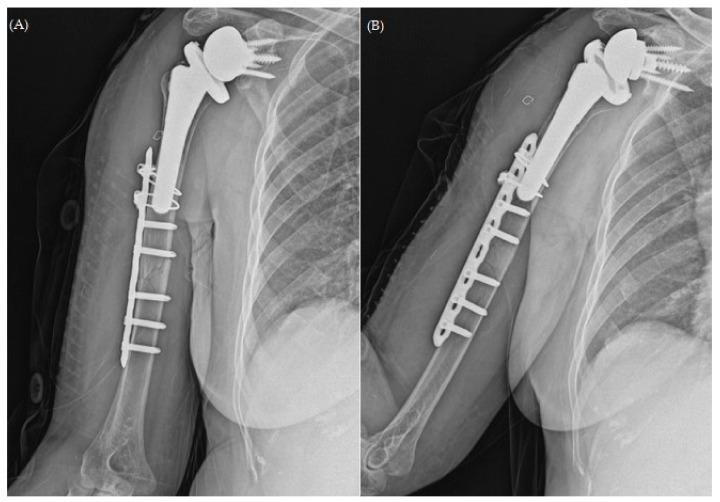

Periprosthetic fractures are a serious complication of joint replacement surgery. With the growing prevalence of reverse total shoulder arthroplasty (RTSA), the incidence of relatively uncommon periprosthetic humeral fractures has increased. Here, we present the unique case of a 74-year-old woman who developed atrophic non-union after plate osteosynthesis for a periprosthetic fracture associated with RTSA. Fixation failure was evident 3 months after the surgical intervention; the patient underwent a 3-month course of arm sling immobilization. However, bone resorption continued, and varus angulation of the fracture developed. In this case, surgical strategy involved the use of long proximal humerus internal locked system plate (DePuy Synthes, Paoli, PA, USA), augmented with autologous iliac bone graft and allogenic humerus structural bone graft with the "bamboo support technique", fixed with Cable System (DePuy Synthes, Paoli, PA, USA). No reports have addressed the management of failed periprosthetic fractures using allogeneic humeral strut bone grafts. This report aims to fill the gap by presenting a novel surgical technique for the management of periprosthetic fractures associated with RTSA in case of treatment failure.

假体周围骨折是关节置换手术的一种严重并发症。随着反式全肩关节置换术(RTSA)的日益普及,相对罕见的假体周围肱骨骨折的发生率有所增加。在此,我们报告一例独特病例,一名74岁女性在因与RTSA相关的假体周围骨折行钢板内固定术后发生萎缩性骨不连。手术干预3个月后固定失败;患者接受了为期3个月的手臂吊带固定治疗。然而,骨吸收仍在继续,骨折出现内翻成角。在该病例中,手术策略包括使用肱骨近端加长锁定系统钢板(美国宾夕法尼亚州波利市DePuy Synthes公司),采用“竹节支撑技术”辅以自体髂骨移植和同种异体肱骨结构性骨移植,并使用线缆系统(美国宾夕法尼亚州波利市DePuy Synthes公司)进行固定。尚无关于使用同种异体肱骨支撑骨移植治疗失败的假体周围骨折的报道。本报告旨在通过介绍一种治疗失败情况下处理与RTSA相关的假体周围骨折的新颖手术技术来填补这一空白。